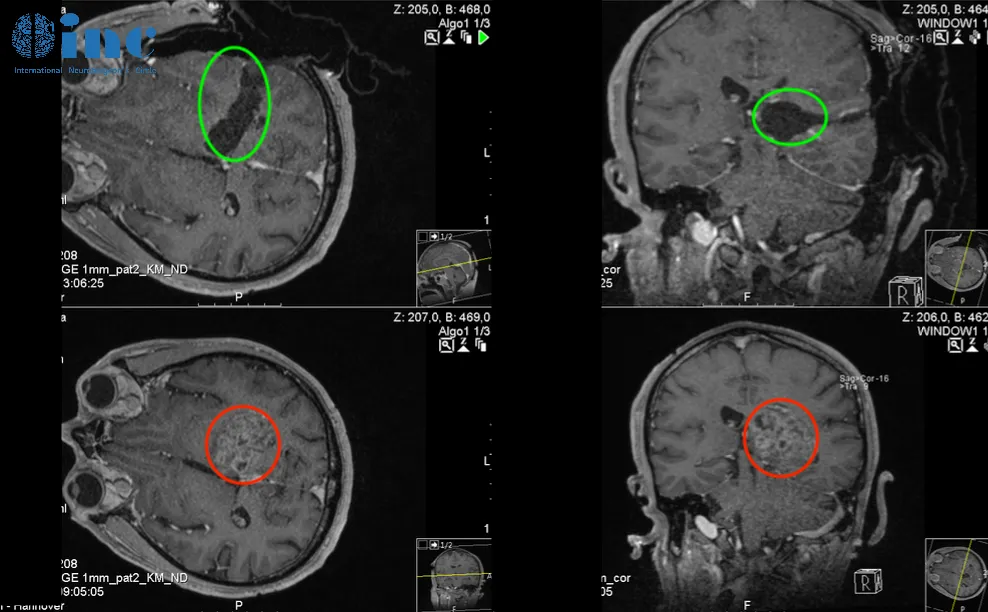

钢琴家丘脑胶质瘤手指障碍,全切术后第5天可自行行走

患者情况:作为钢琴演奏家、钢琴老师的Z女士,大约4个月前发现出右手弹奏不灵活,精细活动限制,头部右侧和右脚麻木感,也偶有视力模糊、有雾感,起初本以为是太劳累所致,却不见好转,当地医院就诊,在当地医院发现颅脑内巨大占位,考虑胶质瘤可能。

主刀医生:INC巴特朗菲教授

治疗后情况:在5-ALA荧光、术中神经导航和术中MRI辅助手术,通过左侧顶枕枕骨开颅术和显微外科肿瘤全切手术,手术顺利,无手术并发症。患者术后当天即拔出气管插管,无任何问题,转入ICU观察1天。术后第2天指标正常迁出ICU。术后第3天即在物理治疗下增加康复锻炼,下地锻炼,术后第5天即可自行站立行走。住院期间,手精细功能障碍、言语和感觉偏瘫均得到改善。右手的精细运动技能也比手术后开始时明显改善。